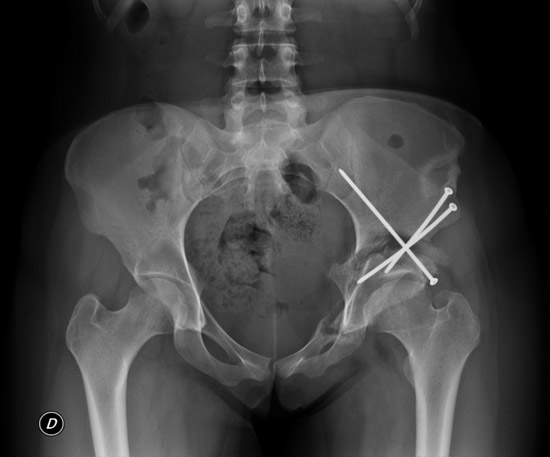

Final strategy decision: Peri-acetabular osteotomy

Peri-acetabular oteotomy

Unfortunately, the patient presented with a non-union of the peri-acetabular osteotomy. A good consolidation was obtained with iliac bone autograft.

The patient is now free of pain with a complete range of motion.

Iliac bone autograft